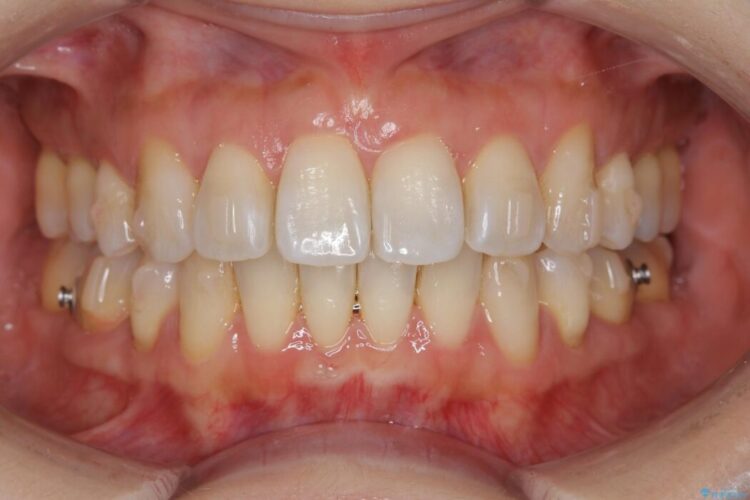

抜歯矯正後の上の前歯の後戻りが気になるとご来院された患者様です。

インビザラインモデレートで治療が可能と診断し、矯正治療を行いました。

歯と歯の間を削るのと、歯列のU字型のアーチを僅かに外側に広げる事でスペースを作り、前歯の角度の改善をしました。

保定装置は、マウスピースと前歯の裏側を細いワイヤーで固定(ボンディングリテーナー)を併用していただいてます。